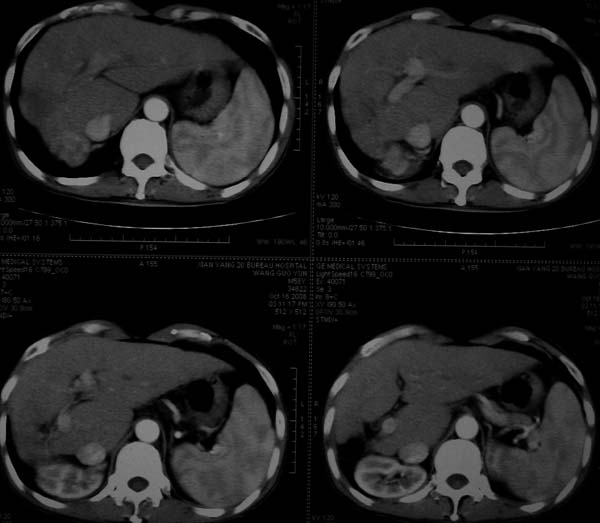

标题: CT16292:男,53岁,上腹部不适2月,B超发现肝内占位病变。 [打印本页]

标题: CT16292:男,53岁,上腹部不适2月,B超发现肝内占位病变。

符合肝ca增强,\"快进快出\";肝叶比例失常,右叶萎缩,肝裂增宽,脾大,肝硬化可能.

肝脏体积变小,肝裂增宽,分布异常,肝尾叶增大,脾肿大,考虑肝硬化可能性大,右肝病灶呈现早期充盈,延迟强化考虑肝内胆管细胞癌可能,不除外血管瘤

肝叶比例失调,左叶增大,肝裂增宽,脾脏增大,门脉增宽,肝右叶包膜下多发结节样阴影,增强虽说强化幅度不大,但还是符合快进快出特点;考虑肝硬化、脾大、结节型肝癌。胆管细胞癌多有延时强化、肝包膜凹陷征、周围胆管扩张等特点,本例明显不符;故不考虑。